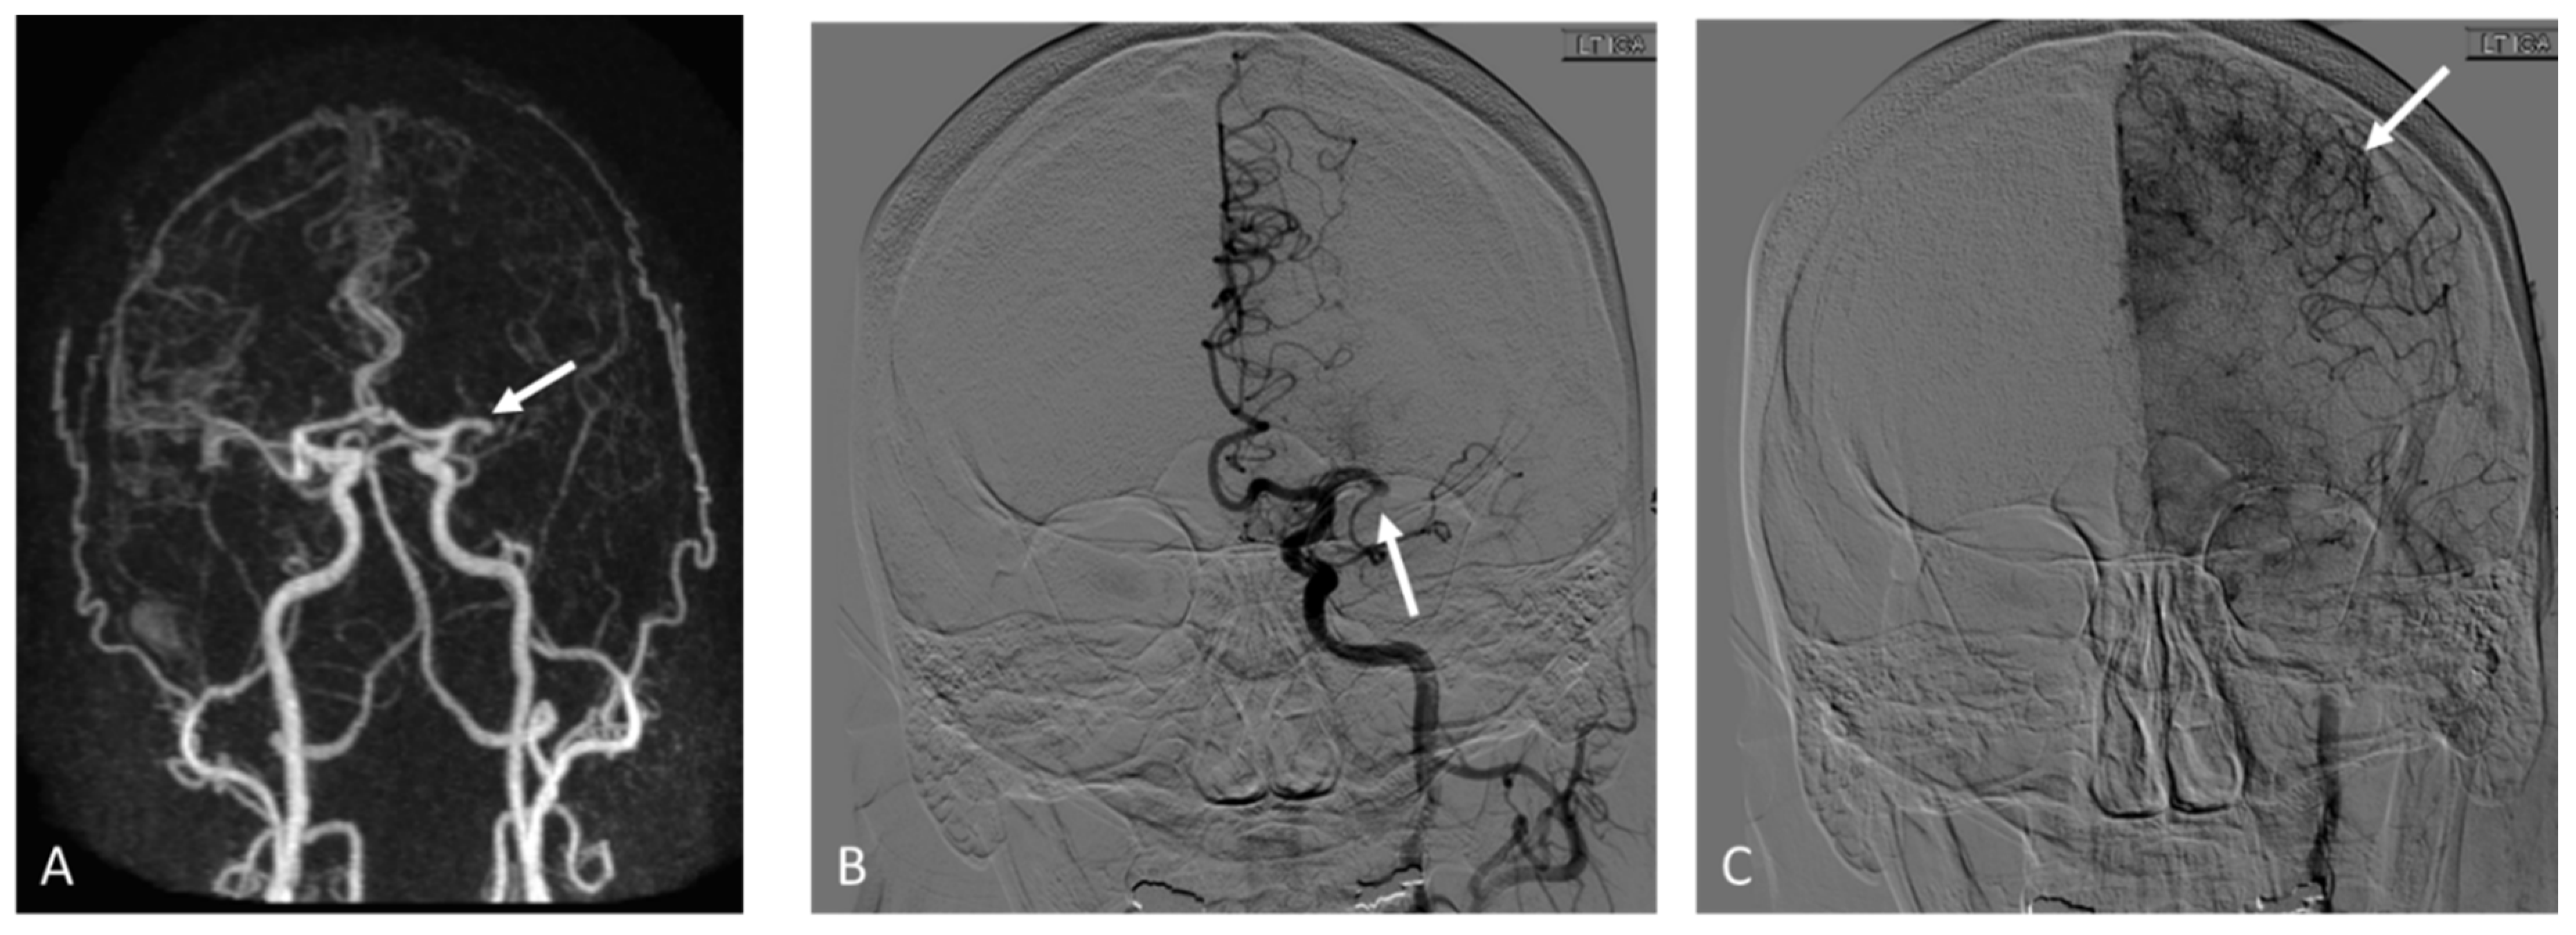

2.3.1. MRA

2.3.2. DSA